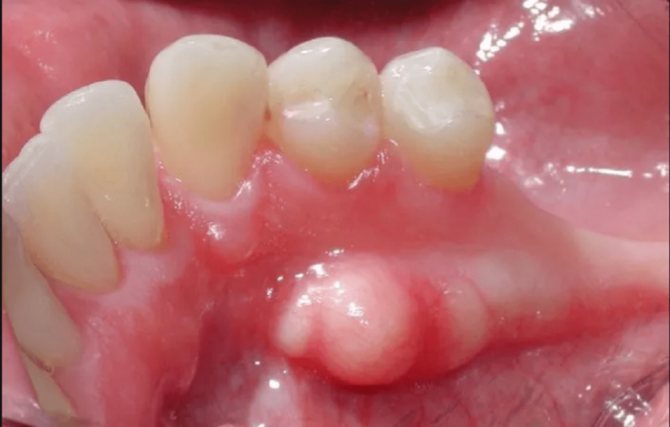

Екзостоз – це хрящової наріст. З’явитися він може на будь-який кістки, в тому числі і на щелепної. Це утворення не відноситься до злоякісних і не становить серйозної загрози для здоров’я. Однак розростається екзостоз здатний травмувати зубні коріння, тому нерідко виникає необхідність в позбавленні від цього наросту. Екзостоз на яснах після видалення зуба

Зазвичай при невеликих розмірах остеофитов скарг у пацієнтів не буває. Їх виявляють при огляді та підготовці до протезування. Рот у пацієнтів з екзостозами відкривається вільно. Слизова оболонка над виростами не змінена, рухома.

При истончении слизової, яке спостерігається при збільшенні екзостозів, підвищується ризик її травмування ортопедичними конструкціями . При пальпації вирости відчуваються як щільні освіти з гладкою або горбистою поверхнею, що не спаянни з навколишніми тканинами.

- На яснах утворюється піднесення. Воно вкрите слизистою оболонкою.

- Новоутворення поступово збільшується в розмірах. Якщо невеликий наріст не доставляв дискомфорту, то наявність великої шишки в роті заважає правильному розташуванню мови. Пацієнт постійно відчуває відчуття присутності стороннього предмета в ротовій порожнині.

- Слизові, що покривають виріст, змінюють колір – стають яскраво-рожевими.

Екзостоз є кістковий виступ на яснах, який виходить у підстави зубів. Він може з’явитися зовні на будь-якій ділянці. Нерідко круглі або гострі шишечки виявляються на небі або відчуваються прямо під язиком. Зазвичай хворобливі симптоми відсутні і людина абсолютно випадково намацує їх зубною щіткою або пальцем. Характерні ознаки розвитку в роті такого кісткового шипа: